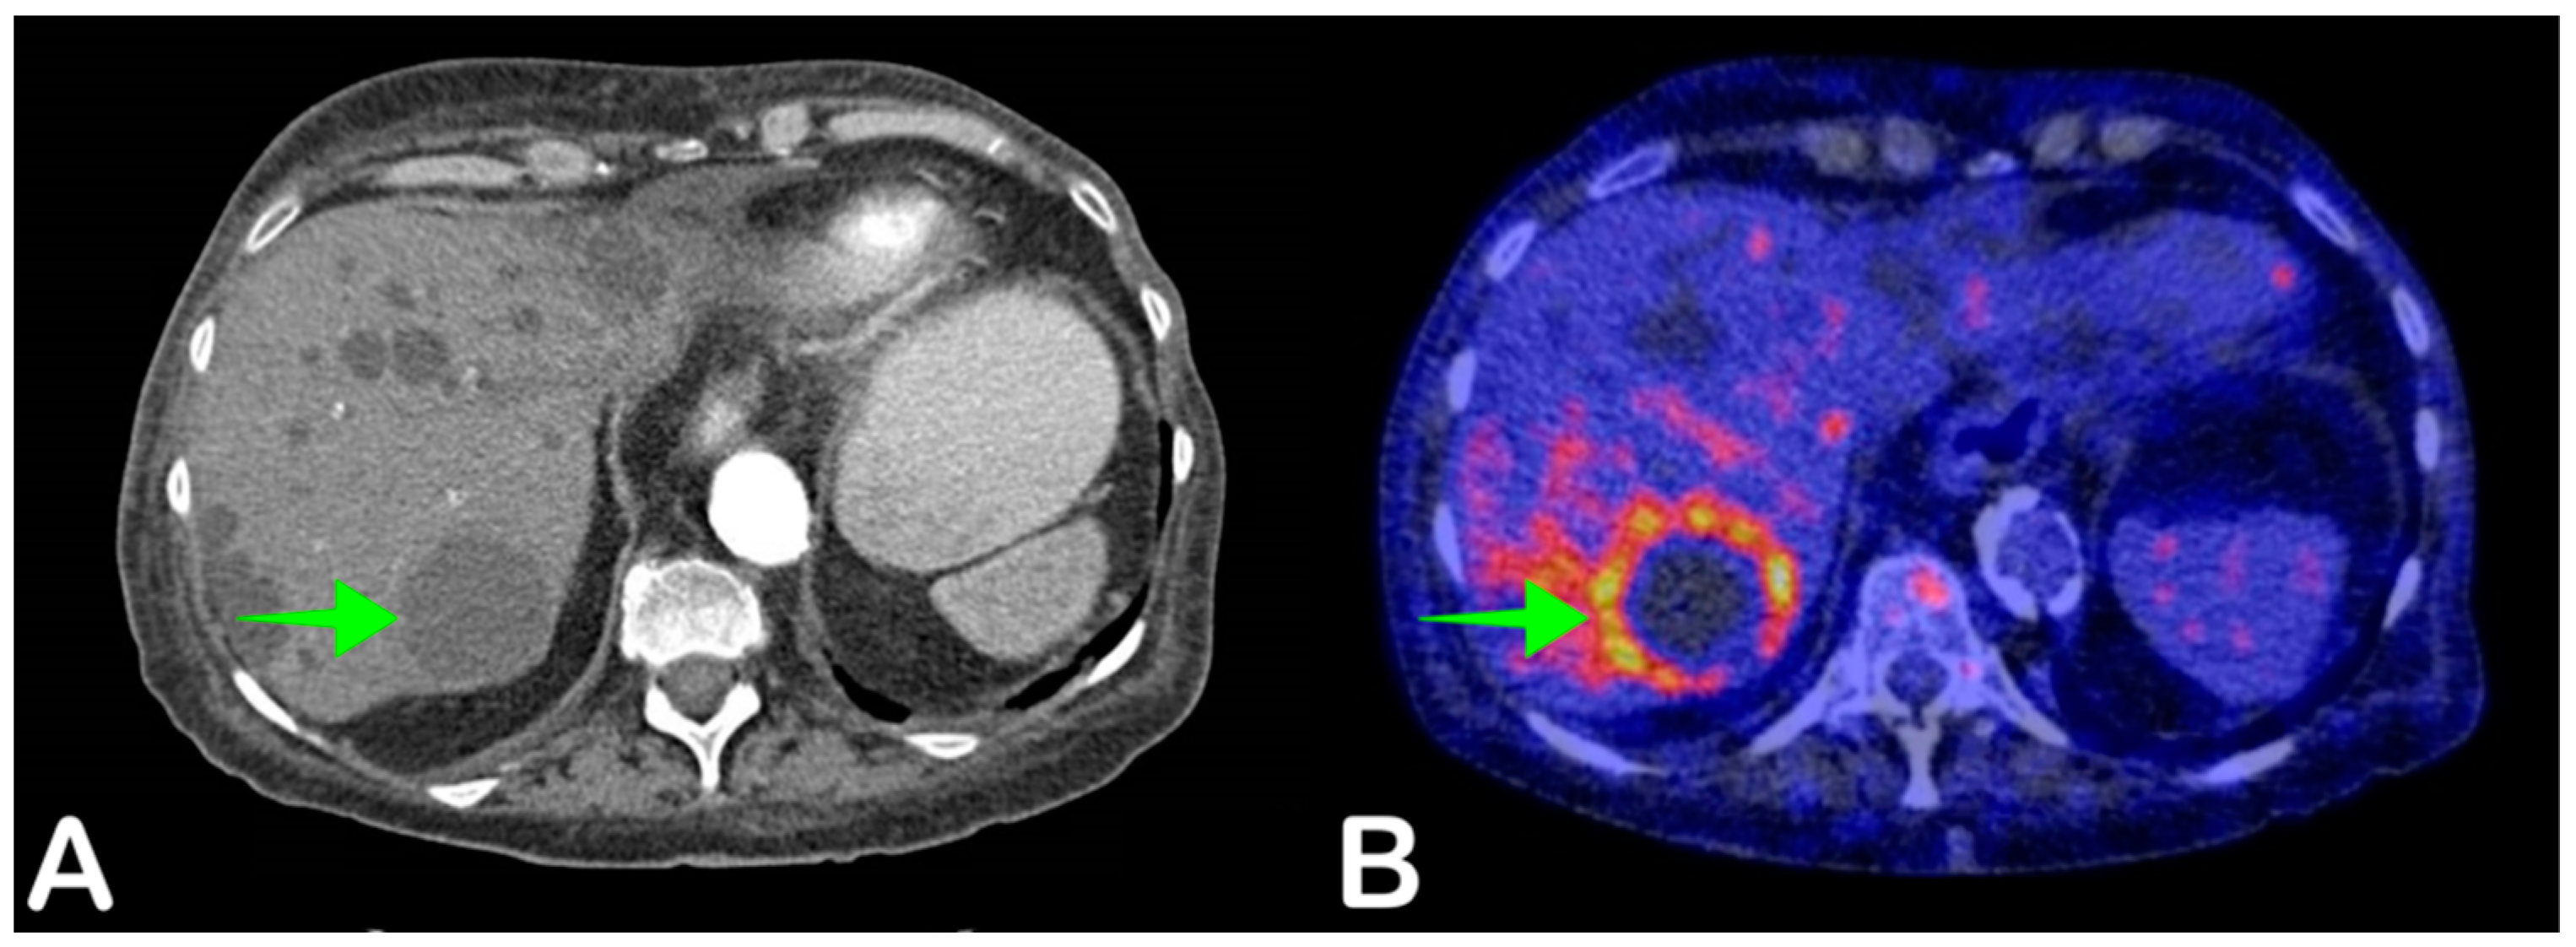

2.6. Cyst Infection

- Pijl, J.P.; Glaudemans, A.W.; Slart, R.H.; Kwee, T.C. 18F-FDG PET/CT in Autosomal Dominant Polycystic Kidney Disease Patients with Suspected Cyst Infection. J. Nucl. Med. 2018, 59, 1734–1741. [Google Scholar] [CrossRef] [Green Version]